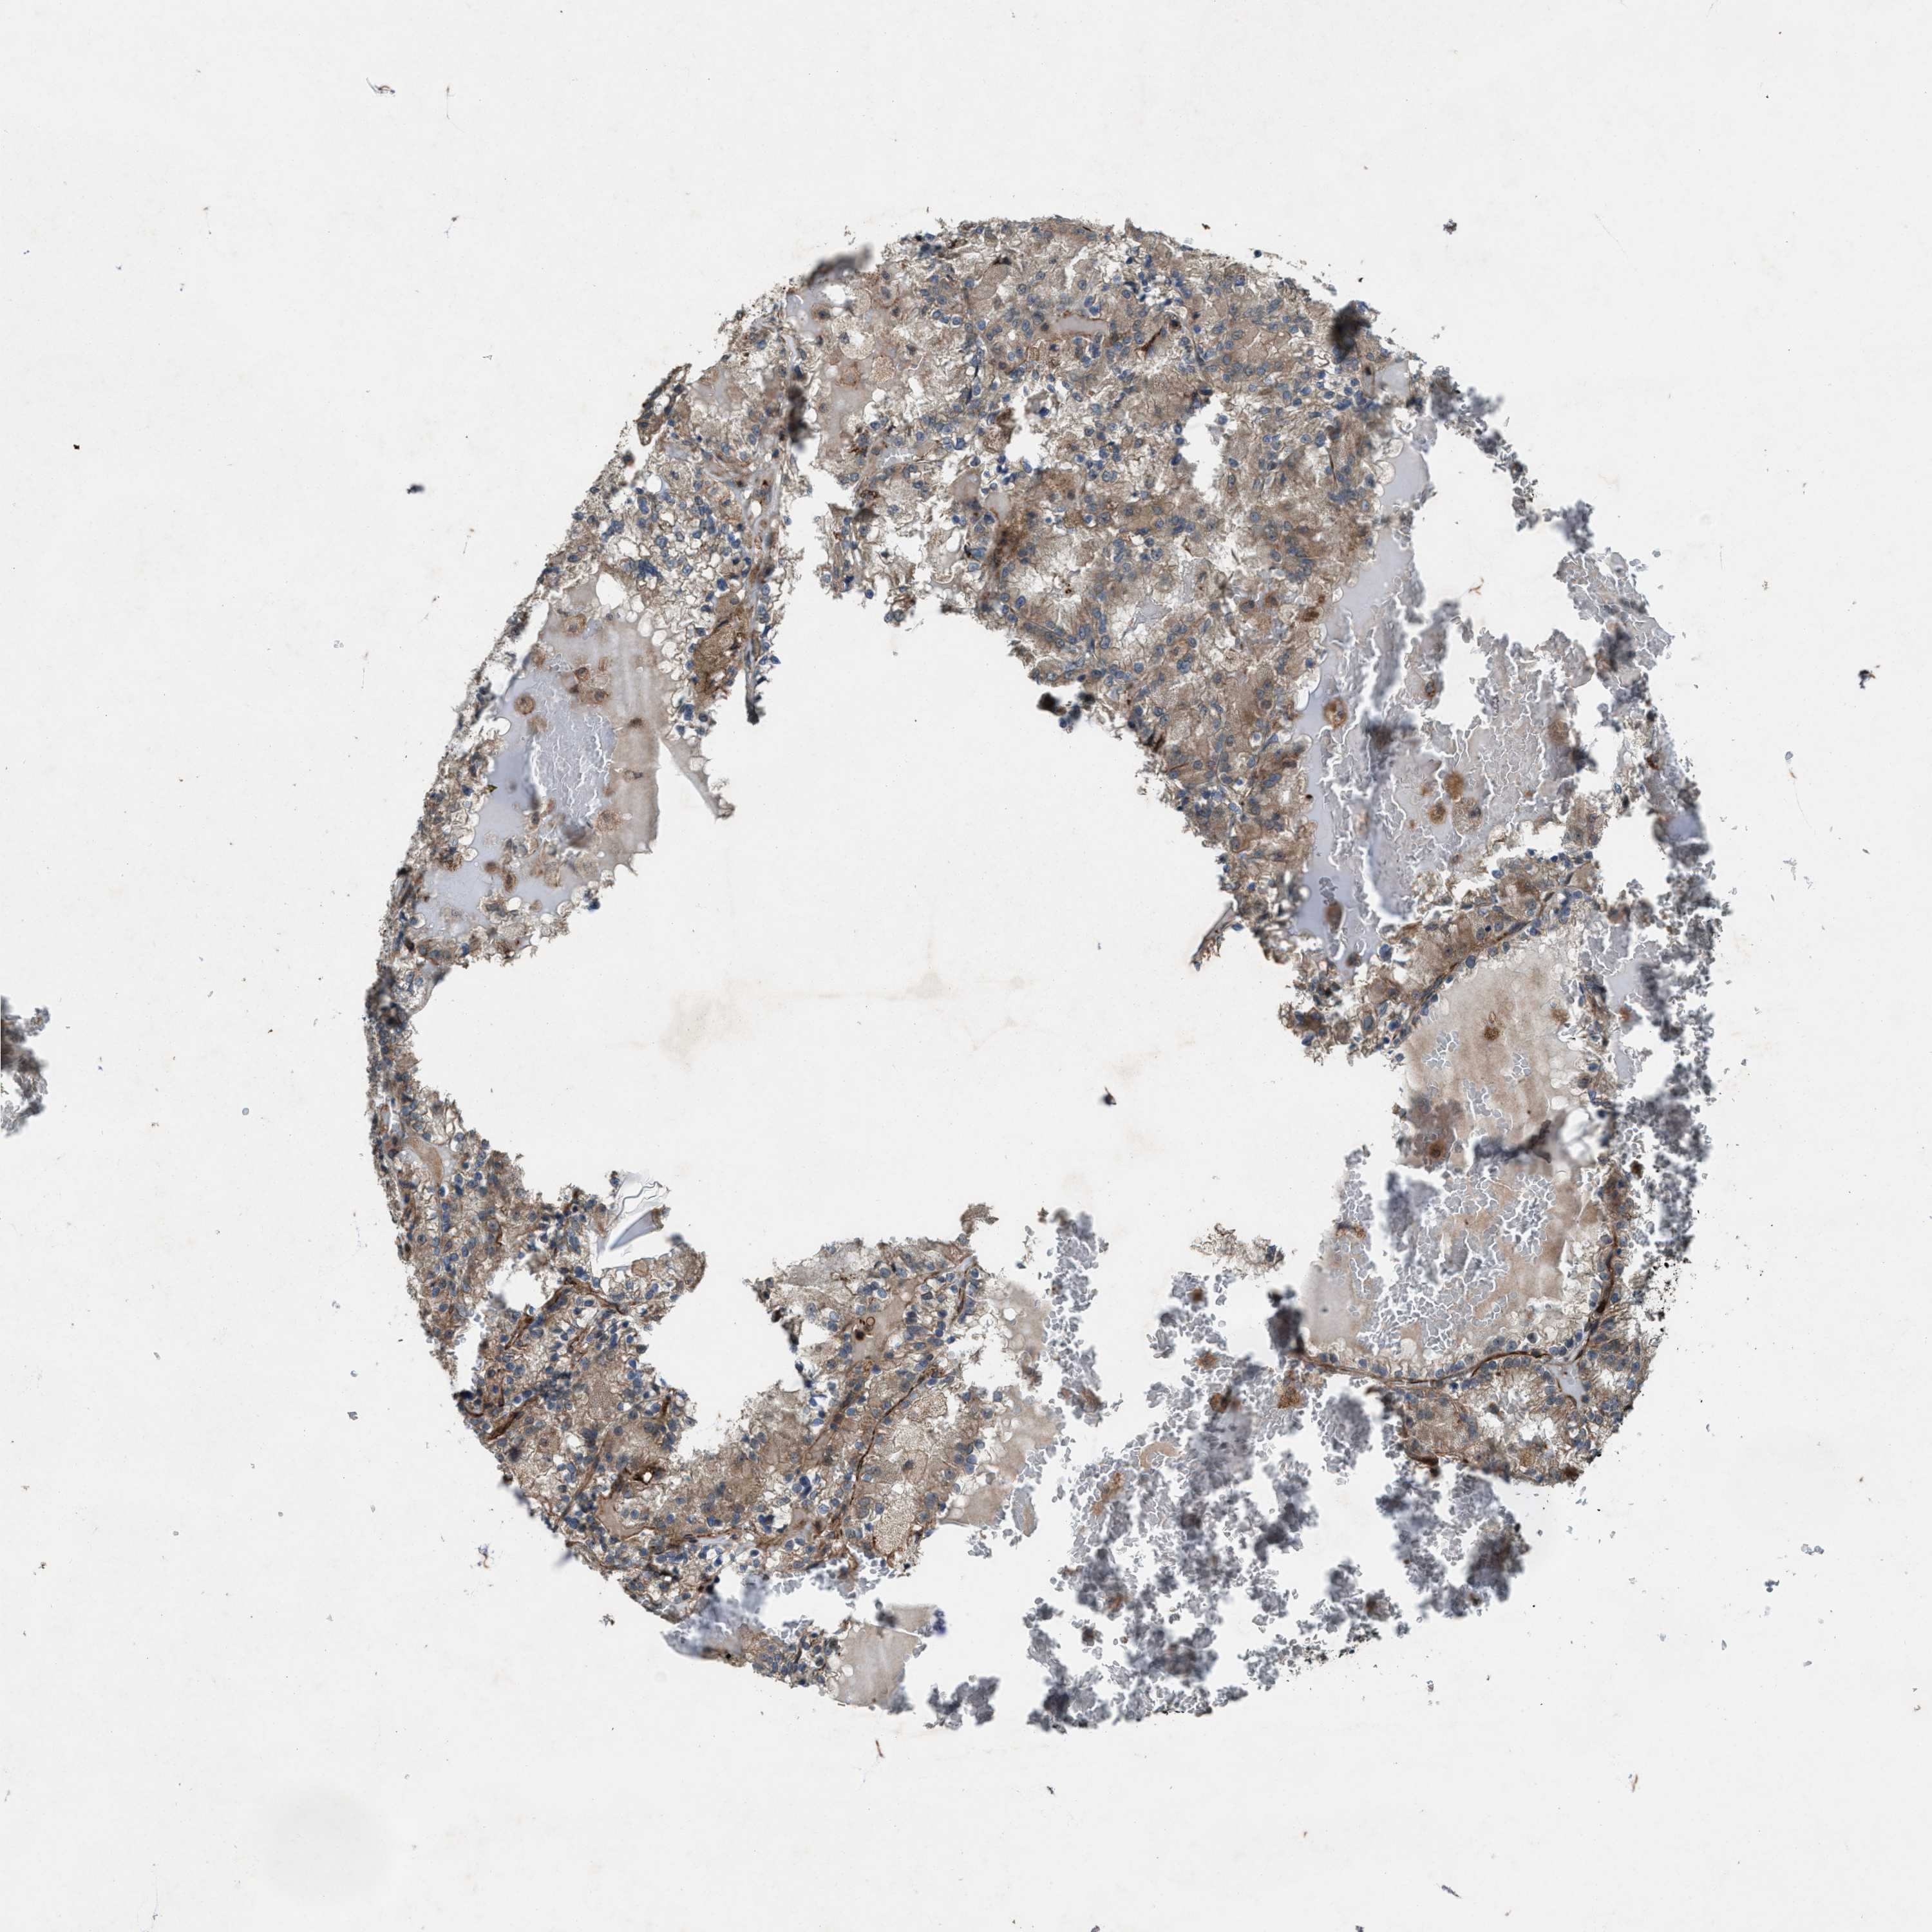

KIDNEY RENAL CLEAR CELL CARCINOMA (VALIDATION) - Interactive survival scatter ploti

The Survival Scatter plot shows the clinical status (i.e. dead or alive) for all individuals in the patient cohort, based on the same data that underlies the corresponding Kaplan-Meier plots. Patients that are alive at last time for follow-up are shown in blue and patients who have died during the study are shown in red.

The x-axis shows the expression levels (FPKM) of the investigated gene in the tumor tissue at the time of diagnosis. The y-axis shows the follow-up time after diagnosis (years). Both axes are complimented with kernel density curves demonstrating the data density over the axes. The top density plot shows the expression levels (FPKM) distribution among dead (red) and alive patients (blue). The right density plot shows the data density of the survived years of dead patients with high and low expression levels respectively, stratified using the cutoff indicated by the vertical dashed line through the Survival Scatter plot. This cutoff is automatically defined based on the FPKM cutoff that minimizes the p-score. The cutoff can be changed by dragging the vertical line or by entering a cutoff value in the square labeled "Current cut-off".

Under the Survival Scatter plot the p-score landscape (black curve; left axis) is shown together with dead median separation (red curve; right axis). Dead median separation is the difference in median mRNA expression between patients who have died with high and low expression, respectively. It is calculated as follows: median FPKM expression of dead patients with high expression - median FPKM expression of dead patients with low expression. This is intended to aid the user in visually exploring custom cutoffs and the associated p-scores and dead median separation.

Individual patient data is displayed and can be filtered by clicking on one or more of the category buttons on the top of the page. Categories describing expression level and patient information include: high, low, alive, dead, female, male and tumor stages. The scale of the x-axis can be toggled between linear and log-scale by clicking on the "x log" button. Mouse-over function shows TCGA ID, patient information and mRNA expression (FPKM) for each patient.

& Survival analysisi

Kaplan-Meier plots summarize results from analysis of correlation between mRNA expression level and patient survival. Patients were divided based on level of expression into one of the two groups "low" (under cut off) or "high" (over cut off). X-axis shows time for survival (years) and y-axis shows the probability of survival, where 1.0 corresponds to 100 percent.

Survival analysis data not available.

TCGA RNA samplesi

RNA-seq data is reported as average FPKM (number Fragments Per Kilobase of exon per Million reads), generated by the The Cancer Genome Atlas (TCGA) .

Normal distribution across the dataset is visualized with box plots, shown as median and 25th and 75th percentiles. Points are displayed as outliers if they are above or below 1.5 times the interquartile range. FPKM values of the individual samples are presented next to the box plot.

Average pTPM 0.0

Number of samples 100